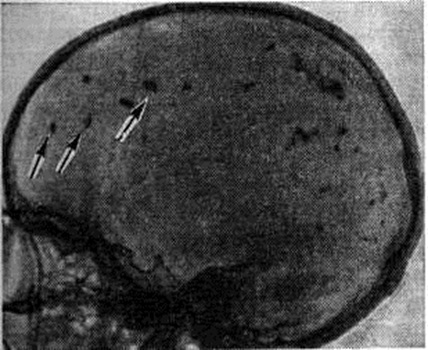

При инфицировании плода незадолго до рождения острая форма болезни продолжается и после рождения ребенка. При прогрессировании болезни преобладает поражение головного мозга. В нем обнаруживаются токсоплазмы, возникают дистрофические изменения, а затем некроз. Экссудативная реакция выражена слабо. Отмечается макрофагальная реакция, в которой участвуют клетки, в основном глиального происхождения, фагоцитирующие возбудителей, и продукты распада некротизированной ткани головного мозга. В кровеносных сосудах — набухание эндотелия, разрастание клеток адвентиции, стаз и нередко тромбоз. В результате поражения сосудов наступает вторичный очаговый асептический колликвационный некроз (смотри полный свод знаний) ткани головного мозга. Очаги некроза имеют различную величину, располагаются асимметрично, преимущественно в коре головного мозга и в субэпендимарной зоне боковых желудочков. При тяжело протекающем процессе эти очаги сливаются в сплошные желтоватые полосы, идущие вдоль извилин головного мозга. Могут выявляться дефекты эпендимы желудочков; сосудистые сплетения и мозговые оболочки нередко утолщены, белесоватого или желтоватого цвета. В дальнейшем массы некроза рассасываются с образованием кист (рисунок 5), которые особенно часто располагаются на границе между серым и белым веществом больших полушарий мозга. В кистах содержится цереброспинальная жидкость, в их стенках обнаруживаются макрофаги, содержащие в цитоплазме продукты распада ткани мозга. По периферии кист обнаруживаются разрастания глии с резким уплотнением вещества головного мозга (смотри полный свод знаний: Киста). Склерозу подвергаются также сосудистые сплетения и мягкая мозговая оболочка. В связи с нарушением оттока цереброспинальной жидкости развивается гидроцефалия (смотри полный свод знаний), достигающая иногда значительной степени. Параллельно с этим происходит обызвествление с пылевидным или зернистым, а иногда массивным отложением солей кальция. При врожденном Токсоплазмоз часто отмечается нарушение развития головного мозга, в частности возможно недоразвитие доли или даже больших полушарий головного мозга.

При рентгенологическое исследованиях на краниограммах больных врожденным Токсоплазмоз могут выявляться признаки гидроцефалии в виде изменения формы и размеров черепа, преждевременного синостозирования швов, уплотнения венечного шва, истончения костей свода черепа (смотри полный свод знаний: Краниография, Череп). Наблюдаются также врождённые дефекты в чешуе лобной и затылочной костей, анизоорбитальный симптом, характеризующийся различной величиной глазных орбит (рисунок 6).

Рис. 6. | ||